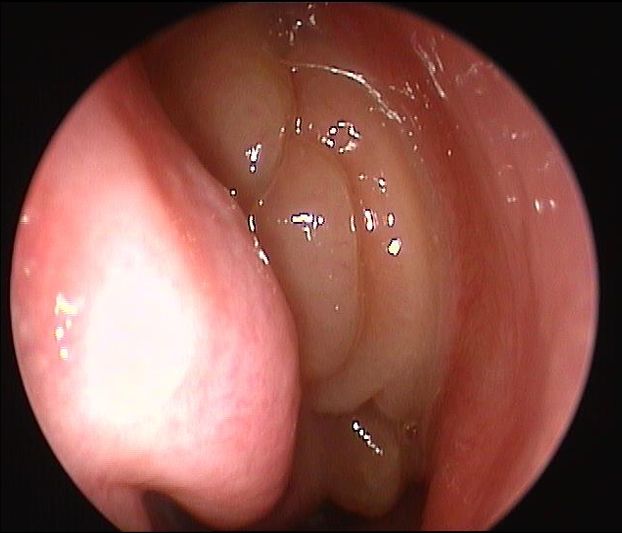

Il FUNGUS BALL:

Si tratta di una forma di sinusite cronica causata dall’accumulo di materiale fungino all’interno di un seno paranasale, più spesso il seno mascellare. Nella maggior parte dei casi, rimane confinato al seno senza invadere i tessuti circostanti.

I sintomi possono essere lievi o aspecifici e includono ostruzione nasale, secrezioni maleodoranti, dolore o senso di peso al volto, spesso da un solo lato. Talvolta la condizione viene scoperta casualmente durante esami radiologici.

La diagnosi si basa su TC dei seni paranasali, che mostra caratteristiche tipiche come aree iperdense all’interno del seno. Il trattamento è chirurgico e consiste nella rimozione del materiale fungino e nel ripristino della normale ventilazione del seno. Dopo l’intervento, la guarigione è generalmente completa senza necessità di terapia antifungina sistemica.